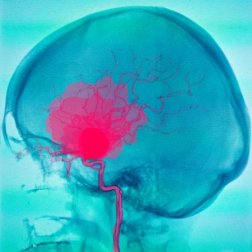

Die harte Hirnhaut, die Spinnwebshaut und die weiche Hirnhaut sind die drei Gehirnhäute, die das menschliche Gehirn umschließen. Eine Subduralblutung (auch Subduralhämatom oder kurz SDH) ist eine Blutung zwischen der harten Hirnhaut und der Spinngewebshaut. Von einer Subarachnoidalblutung (kurz SAB) spricht man bei einer Blutung zwischen der Spinnwebshaut (mittlere Hirnhaut) und der inneren Hirnhaut (Pia mater).

Wenn es zu einer Blutung zwischen den Hirnhäuten kommt, drückt das Blut von außen auf das Gehirn, was lebensbedrohlich sein kann. Abhängend davon, ob die Blutung subdural oder subarachnoidal ist, entstehen verschiedene Krankheitsbilder, die eine sofortige Behandlung erforderlich machen.

In diesem Fall entsteht die Blutung zwischen Arachnoidea und Pia mater. In den meisten Fällen entsteht die Subarachnoidalblutung durch das Aufreißen eines Aneurysmas, doch es können dafür auch andere Gefäßfehlbildungen veranwortlich sein.